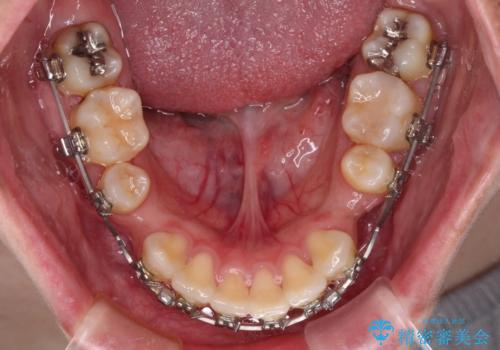

- 矯正装置

- メタルブラケット

- 治療期間

- 2年6ヶ月

下顎骨の左右差や、上顎骨の前方位などが認められたため、上下左右の第1小臼歯4本を抜歯し、ワイヤー装置にて矯正治療を行うこととしました。